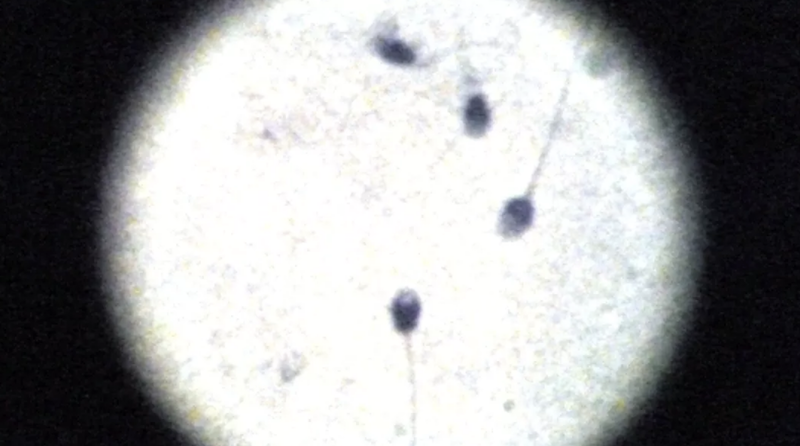

656 alany bevonásával – akik közül 53% hordott boxert -, vizsgálták a WHO sztenderdeknek megfelelően a spermiumokat, a jó minőségű geci feltétele, hogy a spermiumok normál alakúak legyenek, ovális fejjel és a fejméret kb. 5 mikrométer hosszú és 2,4 mikrométer széles legyen.

A 18 és 56 év közötti, ivarérett és szaporodásképes felnőtteknél az jött ki, hogy 25%-kal magasabb volt a spermaszám a boxeralsósoknál, egyetlen ejaculátumban 33%-kal több úszóképes spermium volt, összességében 17%-kal volt jobb a totál spermaszám. Ugyan azt találták, hogy nincs szoros korreláció a szoros alsó és a DNS töredezettsége között, de a magasabb FSH szint ellenére is gyengébb a szaporítóképesség.